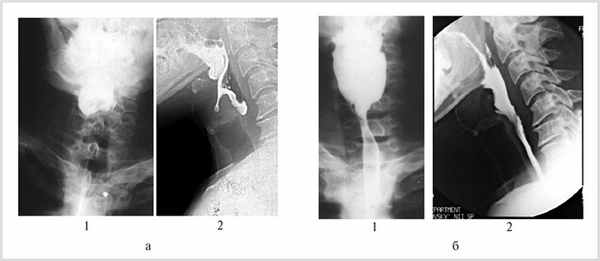

Рентгенологическое исследование заключалось в контрастном исследовании глотки и пищевода в двух проекциях. Из-за угрозы аспирации исследование проводили при попытках проглотить небольшое количество водорастворимого контрастного вещества. Результаты исследования фиксировали на рентгеновской пленке, в 20 наблюдениях проводили видеозапись. При анализе видеоматериала четко отмечено отсутствие поступления контрастного вещества в пищевод (рис. 1, а) и его маятникообразное движение в ротоглотке с забросом в трахею и бронхи.

Рис. 1. Рентгенограммы больного с ахалазией верхнего пищеводного сфинктера. а — до операции. Контрастное вещество в пищевод не поступает (1 — прямая, 2 — боковая проекции); б — через 1 мес после операции. Свободное поступление контрастного вещества в пищевод (1 — прямая, 2 — боковая проекции).

Эти данные были подтверждены результатами рентгенологического исследования. У 12 больных с полностью восстановленным актом глотания отмечалось свободное поступление контрастного вещества из глотки в пищевод (см. рис. 1, б). Просвет глоточно-пищеводного перехода у них был не менее 8 мм в диаметре. У 13 больных с хорошим и удовлетворительным результатом операции проходимость пищевода для водорастворимого контрастного вещества и взвеси сульфата бария восстановилась через 1—3 нед после операции, после упорной тренировки пациентов.